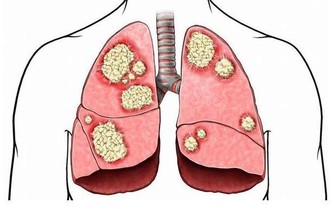

尤其是普洱茶,研究發現普洱茶有助於殺死癌細胞。